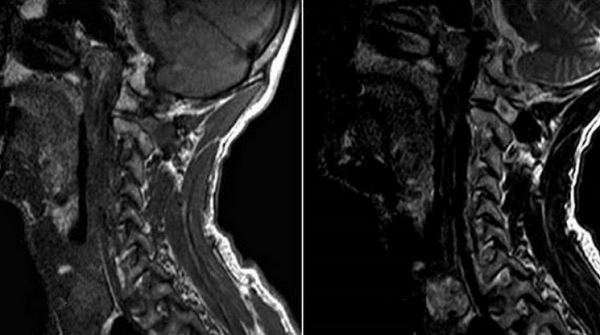

Видно ли на МРТ рак щитовидной железы?

Благодаря резонансному движению заряженных частиц в ответ на воздействие магнитного поля метод визуализируют структурное перерождение тканей, изменение формы, размеров, контуров сканируемого органа. Послойные фотографии, сделанные в аксиальной, фронтальной и сагиттальной проекциях, отображают малейшие трансформации щитовидной железы, включая патологии кровеносных сосудов.

Основными признаками злокачественной опухоли на МРТ являются:

неоднородная структура образования, наличие кист и кальцинатов;

размытый ореол вокруг опухоли (что свидетельствует о перифокальном отеке паренхимы железы);

отсутствие четкой границы между пораженными и здоровыми тканями, инфильтрация атипичных клеток в окружающие структуры;

особенности кровообращения: собственная сеть сосудов представляет собой сложную запутанную систему с большим количеством анастомозов.

Контрастная МРТ при раке щитовидной железы показывает медленное накопление индикатора, что является признаком малигнизации (озлокачествления) образования.

Метод отражает состояние окружающих тканей, позволяет выявить как первичное образование, так и метастазирование опухоли в регионарные лимфатические узлы, загрудинную область, ткани шеи. Точную локализацию очага и степень прорастания атипичных клеток в соседние структуры устанавливают при помощи трехмерного изображения сканируемой зоны.